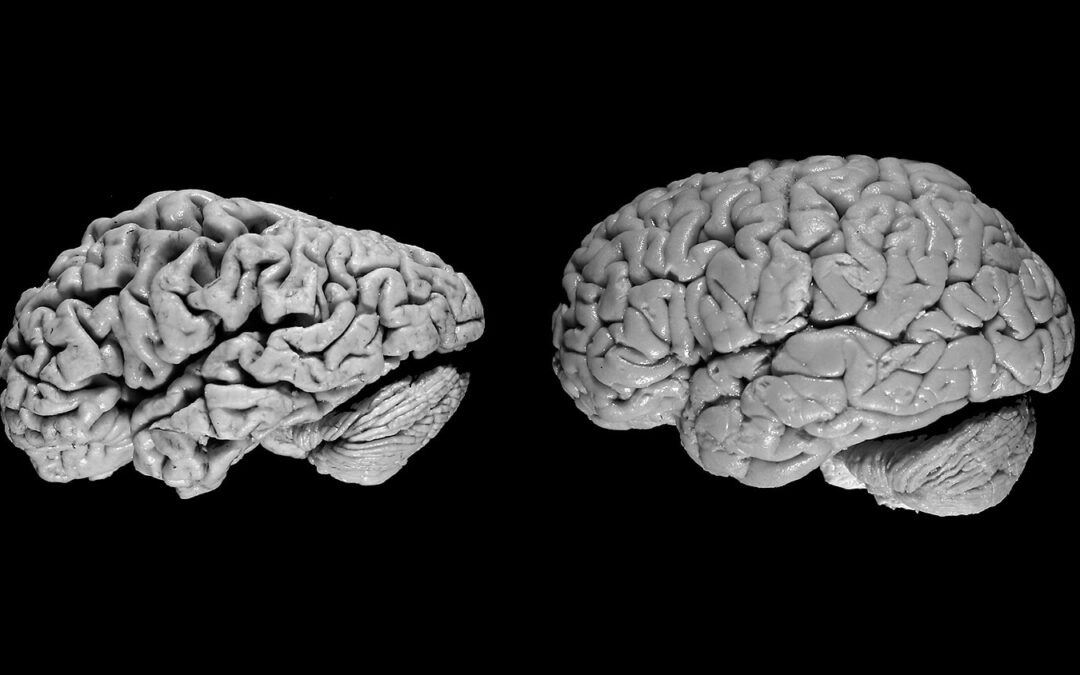

Деменція спричиняється низкою  захворювань, наприклад хворобою Альцгеймера, на яку приходиться до 70  відсотків причин усіх деменцій. В основі цих захворювань лежить прогресуюче пошкодження нервових клітин   та їх зав’язків у мозку, що в призводить до значного погіршення пізнавальних функцій (мислення, пам’ять, увага, мова та ін). Деменція – не є тотожна нормальним проявам старіння, а є захворюванням яке вимагає лікування.

При ХА відбуваються специфічні зміни в головному мозку, включаючи аномальне накопичення бета амілоїдих  та тау білків, детекція яких дозволяє відрізняти дану форму деменції від деменцій викликаних іншими захворюваннями.